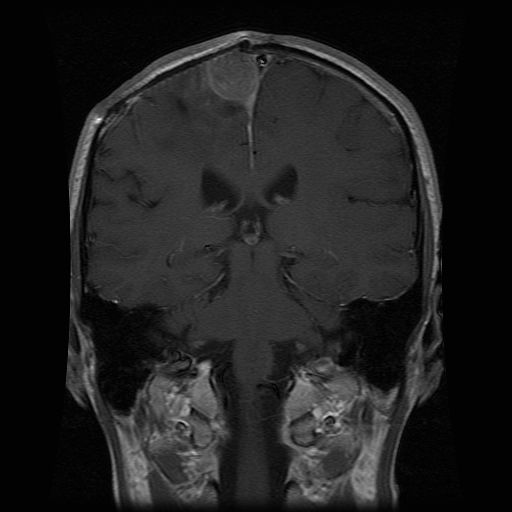

On Monday the report told me what I already knew.  The mass had grown bigger by half a cm all around [top view, ear-to-ear view] in one month.  The radiologist no longer considered it an abscess, but said it was tumor re-growth.  When Dr. Black saw the films he agreed it was tumor, but thought radiation was the next course of action, not surgery.  He seemed a little surprised that I was not doing radiation already.